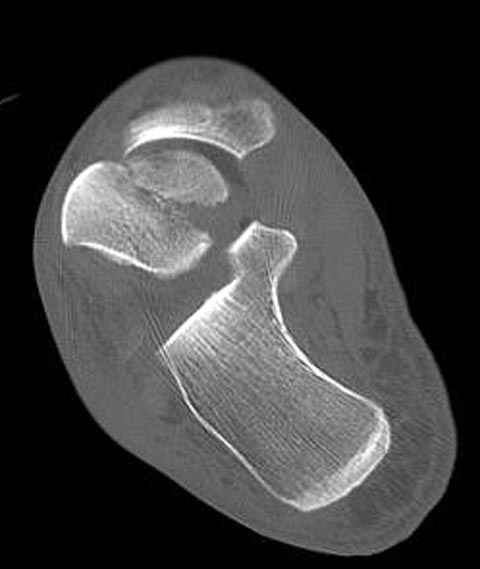

Уважаемые участники русского Ортофорума, поздравляю всех со всеми прошедшими праздниками: Новым годом, Рождеством, Hanukkah, Kwanzaa, желаю участникам всего наилучшего и здоровья.Повреждение таранной кости.Больной 81г автоавария, повреждение таранной кости, здесь снимки.

Вдогонку по поводу перелома таранной кости, больная 81, не страдает диабетом, перелом закрытый, в первый же день поступления ограничились временным наружным фиксатором (как на снимке).

Примеры на снимке...